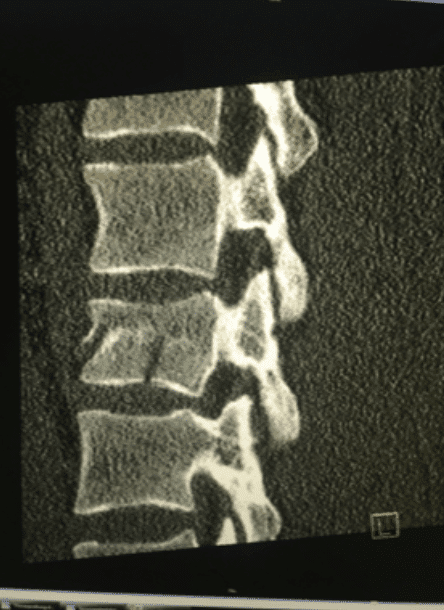

Goerke crashed while jumping through a large triple section and landed extremely short on the jump. The impact of the crash caused the majority of his injuries, fracturing his spine at the L2 vertebrae and broke his left clavicle. He was taken to Klinikum Chemnitz; a local hospital near the Fair where surgeons performed the first of two scheduled surgeries stabilizing his spine with rods. The second surgery to address the left clavicle break is expected to be scheduled this Thursday.